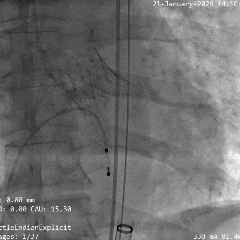

术中影像

根部造影

瓣叶活动差,可见明显反流,猪尾导管测量跨瓣压差约50mmHg

20mm球囊预扩

微腰微漏,左右冠均显影

造影确认瓣环与瓣膜位置

瓣膜0位初始定位释放,展开过程微微下移

全展开位造影评估

瓣膜呈直筒型,微腰,大弯侧约瓣下3mm,少量反流,冠脉显影

瓣膜无张力脱钩

植入后造影评估

瓣膜位置合适,可见少量反流

多角度造影评估

瓣膜形态可,冠脉显影,猪尾测量压差为0